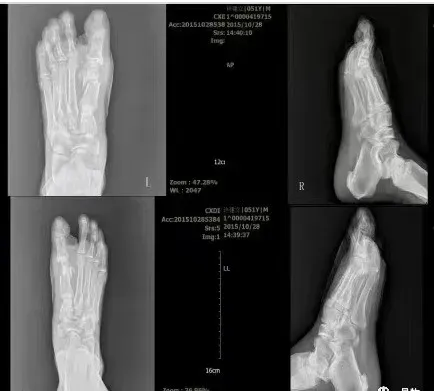

术前术后X光片对比图